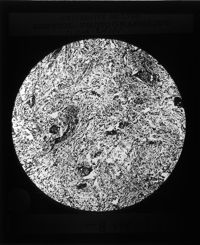

Image[Plaque diapositive. Tissus bucco-dentaires.]